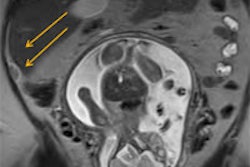

For the phase I trial, 15 patients with medication-refractory essential tremor underwent transcranial MRgFUS thalamotomy targeting the ventral intermediate nucleus. Adverse events were recorded throughout the study, with neurologic assessments for sensation, gait, strength, and balance, according to a release from AANS.

A rating scale for tremor was used to evaluate the procedure's efficacy, and a quality-of-life questionnaire was completed before treatment and at three and 12 months after treatment. Lesions were assessed by MRI one day, one week, one month, and three months following treatment.

The study, presented by Dr. William Jeffrey Elias from the University of Virginia School of Medicine, showed a 67% reduction in contralateral hand tremor at one year. This reduction of tremor in the dominant hand resulted in substantial improvements in daily disabilities (83%) and quality of life.